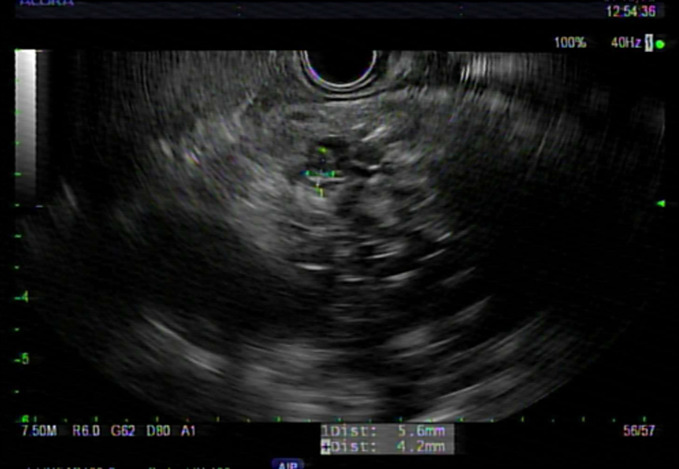

Case presentation: A 60-year-old female with an unremarkable medical history presented with epigastric pain for 2 weeks. Her initial laboratory workup was notable for mild isolated elevation of alkaline phosphatase. Abdominal computed tomography revealed a 5.0 × 4.0 cm cystic lesion in the pancreatic head with thick internal septations. Magnetic resonance cholangiopancreatography showed a 5.2 × 4.5 × 6.8 cm lobulated cystic lesion in the pancreatic head with a microcystic configuration, multiple internal septations, and a hypointense central scar. Endosonographic examination showed a large multicystic lesion in the pancreatic head region. Fine-needle aspiration showed a carcinoembryonic antigen level of 555 ng/mL and an amylase level of 13,593 U/L. No KRAS or GNAS mutations or loss of heterozygosity was detected. Subsequently, the patient underwent a Whipple procedure. Pathologic examination revealed a complex cystic lesion with well-differentiated acinar cells and patches of ductal epithelium compatible with ACC. Histological examination confirmed the presence of low-grade PanIN without invasive carcinoma. The patient recovered well from surgery, and repeat imaging 2 months later was unremarkable.